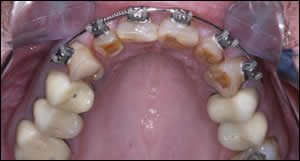

Fig 7: Occlusal views demonstrate the defective restorations, enamel abrasion, and crooked teeth. It was decided that treatment would be restricted to the anterior teeth. A multi-disciplinary approach was essential in achieving a successful functional and esthetic result.

Fig 8: The maxillary anterior teeth were slenderized and orthodontic appliances were inserted.